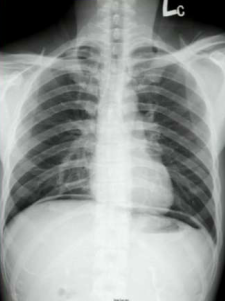

A child presents with fatigue, difficulty breathing and an abdominal mass. What is your diagnosis?

Wilm’s tumor

What does this patient have?

Hepatosplenomegaly